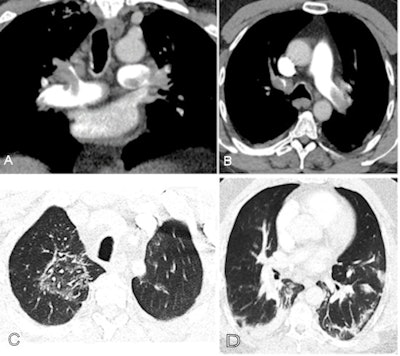

Kaminetzky and colleagues found that 37.1% of CTPA exams performed in patients with confirmed COVID-19 disease identified pulmonary embolism (PE), a much higher rate than those patients in a control cohort who underwent CTPA but did not have the disease (14.5%).

The group also found that D-dimer levels assessed closest to the date of the CTPA exam were higher in patients with COVID-19 and PE, and the D-dimer levels correlated to a higher CT severity score: Mean D-dimer was 1,774 ng/mL D-dimer units (DDU) in patients with CTPAs negative for PE and 6,432 ng/mL DDU in patients with CTPAs positive for PE (p < 0.001).